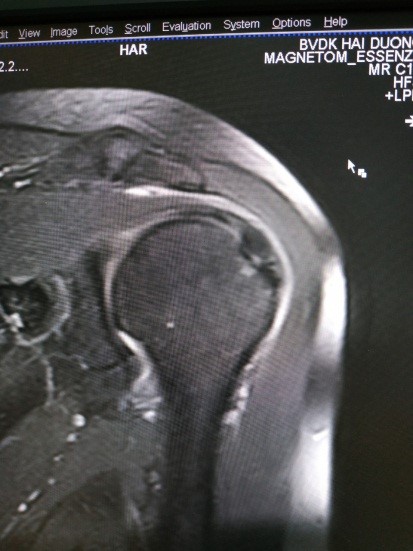

Hình ảnh điển hình tổn thương GCX

Hình 5. Hình ảnh rách bán phần(A), rách hoàn toàn(B)